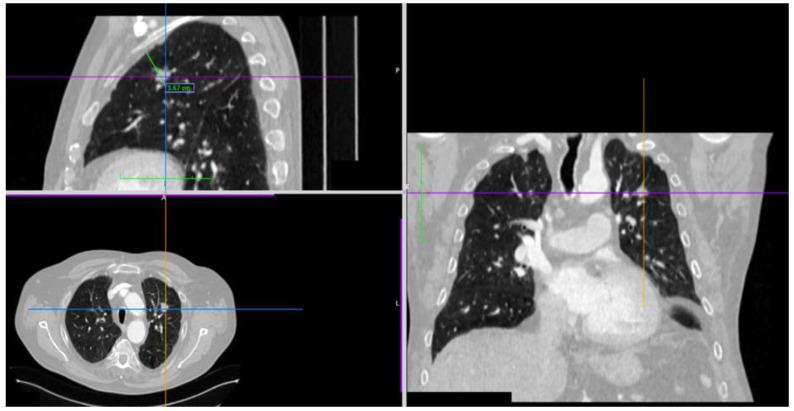

: As part of different navigational bronchoscopy (NVB) modalities, radial-probe endobronchial ultrasound (rEBUS) is used to confirm the peribronchial localization of peripheral pulmonary nodules (PPNs) immediately before collecting samples for histopathological analysis. : This retrospective case series study presents the results of en bloc cryobiopsy of PPNs using a flexible 1.1-mm cryoprobe with different NVB modalities. For PPNs classified as adjacent or eccentric lesions by rEBUS (ES-rEBUS), the cryoprobe's position was adjusted by 90-180° in relation to the ultrasound image of the lesion during the first and second biopsies. : All patients with a final histopathologically confirmed diagnosis of PPNs had positive rEBUS findings, regardless of the navigation modality, eccentric (18/42 patients, 43%) and concentric (24/42 patients, 57%) rEBUS view. In 5 out of 6 patients without a histopathological diagnosis, PPNs were not visualized by radial ultrasound. In the (ES-rEBUS) group of patients, 4 out of 18 had fewer than three biopsy samples collected per procedure, which means only an adjusted probe position has been applied, although diagnostic outcomes were achieved. Common Terminology Criteria for Adverse Events (CTCAE) grade 2 complications were reported in 10.4% of the patients, and grade 3 complications in 2% of the patients. : Confirming the localization of nodules by rEBUS and properly adjusting the cryoprobe immediately before cryobiopsy of PPNs resulted in a diagnostic yield meeting the literature standards.

作为不同导航支气管镜检查(NVB)方式的一部分,在为组织病理学分析采集样本之前,径向探头支气管内超声(rEBUS)用于确认周围型肺结节(PPN)的支气管周围定位。:这项回顾性病例系列研究展示了使用1.1毫米柔性冷冻探头结合不同NVB方式对PPN进行整块冷冻活检的结果。对于经rEBUS(ES-rEBUS)分类为相邻或偏心病变的PPN,在首次和第二次活检期间,冷冻探头的位置相对于病变的超声图像调整90 - 180°。:所有最终经组织病理学确诊为PPN的患者,无论采用何种导航方式,rEBUS检查结果均为阳性,偏心(18/42例患者,43%)和同心(24/42例患者,57%)rEBUS视图。在6例未获得组织病理学诊断的患者中,有5例的PPN未通过径向超声显示。在(ES-rEBUS)组患者中,18例中有4例每次手术采集的活检样本少于3个,这意味着仅应用了调整后的探头位置,尽管达到了诊断结果。10.4%的患者报告了常见不良事件术语标准(CTCAE)2级并发症,2%的患者报告了3级并发症。:通过rEBUS确认结节定位并在PPN冷冻活检前正确调整冷冻探头,诊断率达到了文献标准。